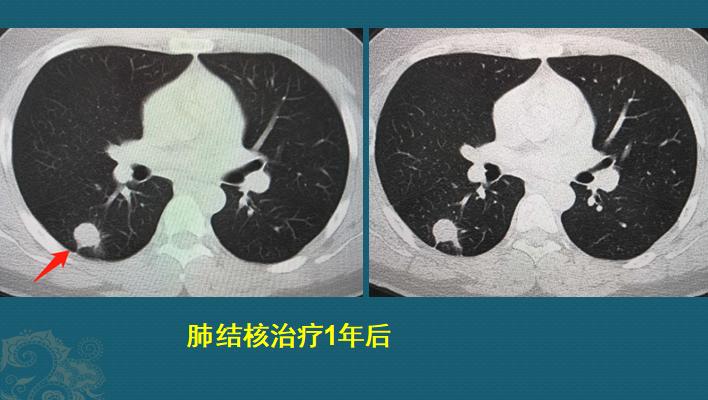

处于活动期的肺结核有传染性,且结核治疗周期长,有些需要休学。这位同学吃了一年抗结核药,最近几个月多次痰检都是阴性,今天复查CT情况,看看能否复学。

对比两次CT片病灶明显好转:空洞闭合,结节缩小并伴有点状钙化,原病灶周围的多发点片影和树芽征都吸收了,支气管也恢复正常。

CT片说明病灶明显好转,处于“稳定期”,还要结合病原学检测,如果都是阴性,加上小伙子已经没有任何症状,就可以复学了。

读到这里大家应该就能明白,这位高三男生已经没有症状,最近几个月痰液里查不到结核杆菌了,肺部CT显示病灶大部分吸收,只残留一个伴有钙化的结节,属于稳定的陈旧性改变,可以安心复学了!